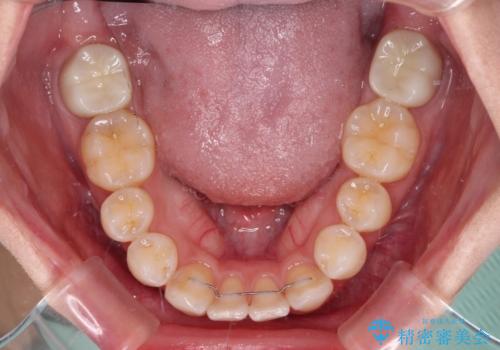

上顎の八重歯と下顎前歯の欠損 ワイヤー装置による抜歯矯正

- 上顎の八重歯を気にして来院された患者様です。

診察したところ、下顎前歯が2本欠損していたため、上下のバランスを取りながら八重歯を改善するため、上顎左右第一小臼歯2本を抜歯することとしました。

下顎左右大臼歯の歯根部に病変があったため、矯正治療前に根管治療を行い、矯正治療後にセラミッククラウンによる補綴治療を行うこととしました。

下顎前歯と本来抜歯矯正で抜歯する歯とは大きさが異なるため、仕上がりの咬み合わせは理想的なものとはなりませんでしたが、気になっていた八重歯はきれいに改善することができました。